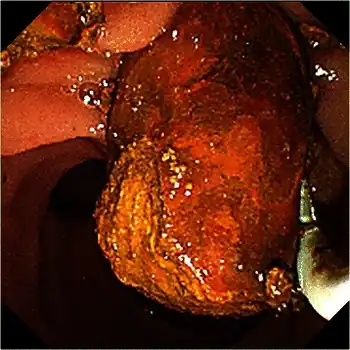

Abdominal ultrasonography of a common bile duct stone

Abdominal ultrasonography of a common bile duct stone Fluoroscopic image taken during endoscopic retrograde cholangiopancreatography (ERCP). Multiple gallstones are present in the gallbladder and cystic duct. The common bile duct and pancreatic duct appear to be unobstructed.